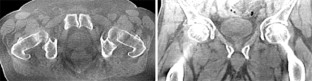

Abb. 4